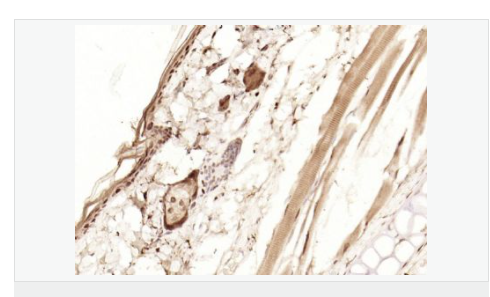

| 產(chǎn)品應(yīng)用 | WB=1:1000-2000 ELISA=1:1000-5000 IHC-P=1:100-500 IHC-F=1:100-500 Flow-Cyt=1ug/Test ICC=1:100-500 IF=1:100-500 (石蠟切片需做抗原修復(fù)) not yet tested in other applications. optimal dilutions/concentrations should be determined by the end user. |